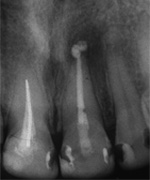

Die ersten beiden Aufnahmen sind aus dem Jahr 1999, die 3. von 2006

Der umfangreiche kariöse Defekt steuerte sehr bald hin auf die komplette Entfernung des Zahninnen­gewebes mit anschliessendem medikamentösen Wiederverschluss. Aufbissempfindlichkeit am Folgetermin ist immer Aufforderung zur erneuten Intensivsuche nach weiteren Kanälen, die hier einen 4. Ast zum Vorschein brachte. Nach 2 ausgelassenen Terminen

waren vorrangig Wiederherstellung von desinfizierender Einlage und provisorischer Füllung angezeigt. Eine weitere Woche später wurde in allen Kanälen das Medikament durch die endgültige Verschlussmasse ersetzt, worauf Zahn 36 mit 12-tägiger Verzögerung erneut zu rebellieren begann. Das hiess aus den hinteren Wurzeln Füllmaterial wieder raus und

Einlage erneut rein. Als es dann 4 Wochen später bei der hinteren Wur­zel aussen anzuschwellen begann und ein Medikamentenwechsel ohne Wir­kung blieb, wurden die hinteren Ka­näle abgefüllt und auch in gleicher Sitzung das überstopfte Material (Bild 1) mittels Resektion (Bild 2) von aussen entfernt.